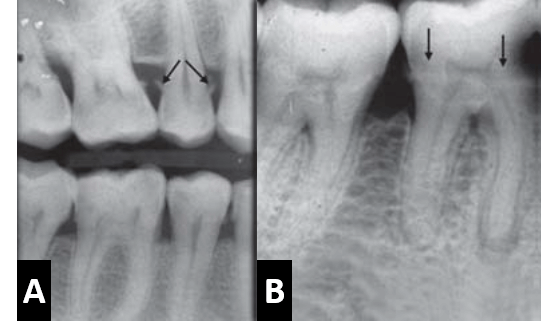

La pérdida ósea atribuida a la enfermedad periodontal puede ser estimada como la diferencia entre la altura ósea fisiológica y la altura de hueso remanente. Cuando está perdida ósea ocurre en áreas aisladas abarcando menos del 30% del hueso de soporte es llamada perdida ósea localizada; mientras que cuando el compromiso óseo se presenta en ambas arcadas dentarias de forma general tanto en la arcada superior como en la inferior con más del 30% de compromiso del hueso de soporte es descrito como una pérdida ósea generalizada. Así también, cuando la pérdida ósea forma un ángulo con un plano imaginario entre la unión cementoadamantina de dos dientes adyacentes, es conocida como reabsorción ósea de tipo vertical o angular; y cuando la perdida ósea se observa de forma paralela con el plano imaginario entre la unión cementoadamantina de dos dientes adyacentes, se conoce como reabsorción ósea de tipo horizontal.

Por otro lado, la extensión de un bolsillo periodontal entre las raíces de un diente multirradicular conllevara al compromiso de la furcación, la cual podrá observarse por medio de una radiografía cuando la reabsorción ósea cuando esta se extienda en sentido apical, mas allá de la furcación. El compromiso óseo de la furcación de una molar mandibular es posible observarla con mayor claridad, a diferencia de un molar superior donde la raíz palatina se superpone sobre la furcación.